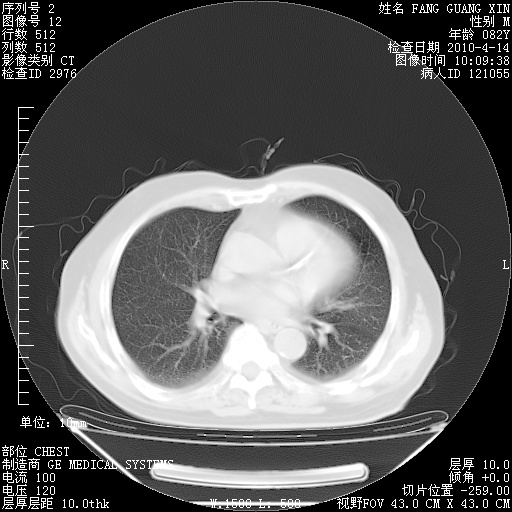

4月14日肺部CT